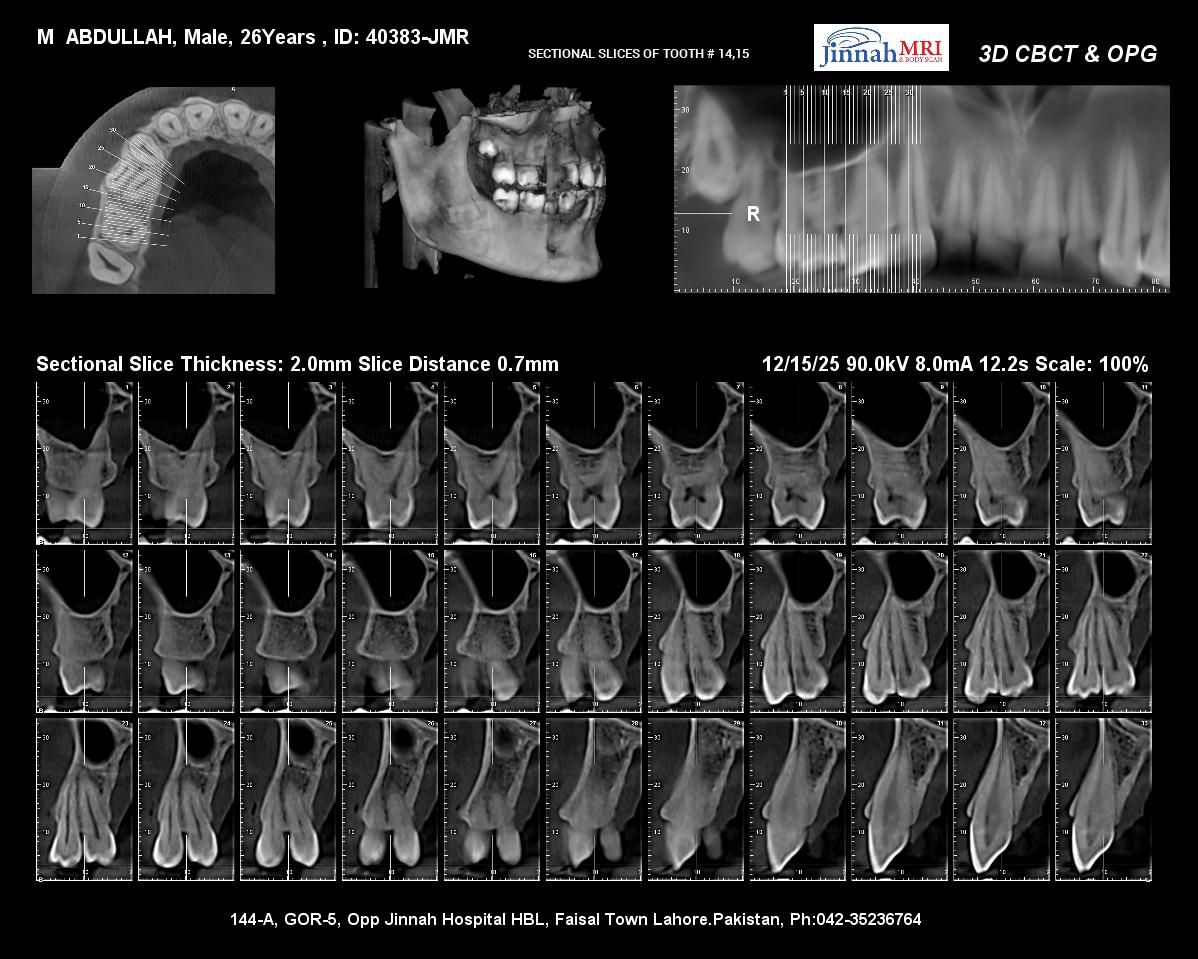

Case evaluation with CBCT for precise diagnosis and optimal treatment outcomes.

Case evaluation with CBCT for precise diagnosis and optimal treatment outcomes.